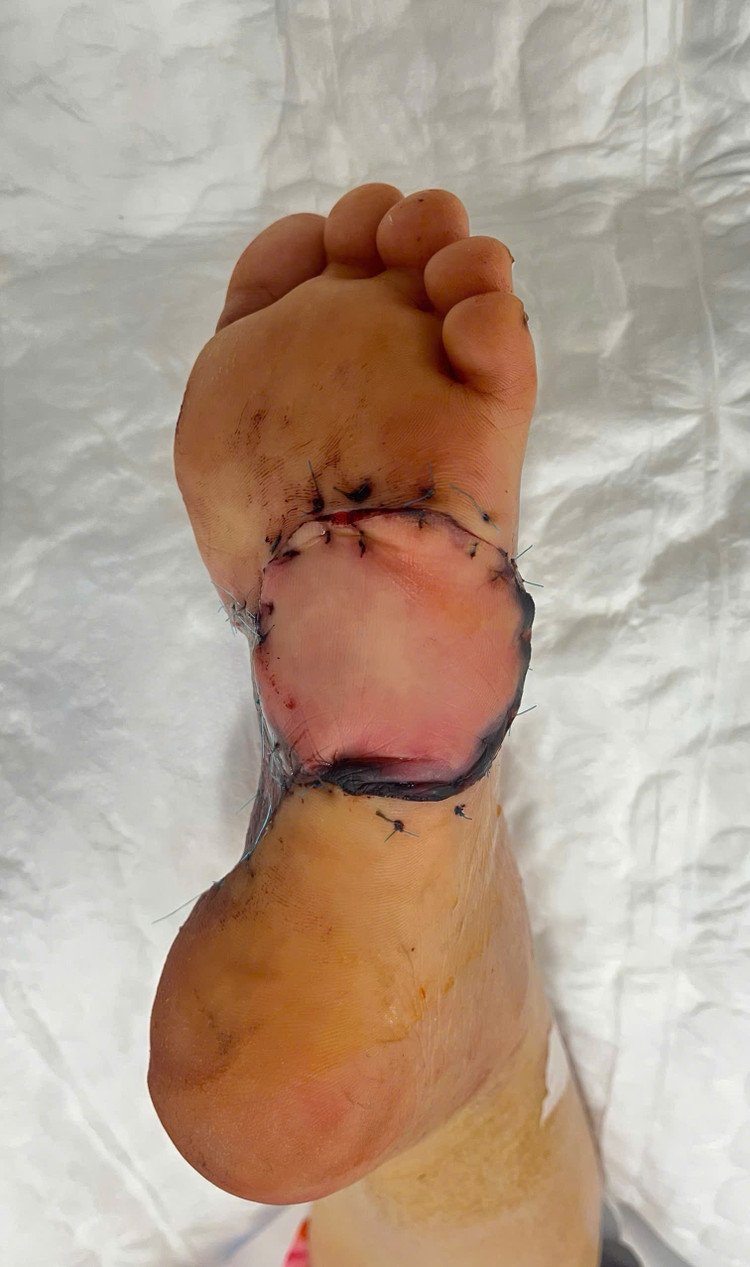

Ê-kíp bác sĩ đã sử dụng vạt da tại vòm gan chân – nơi ít chịu lực – và nuôi dưỡng vạt da bằng động mạch ngược dòng. Sau ba ngày, vạt da hồi phục tốt, vết mổ khô, ổn định, giúp bệnh nhân phục hồi vận động nhanh chóng.

| Tạo hình chân cho bệnh nhân - Ảnh BVCC |